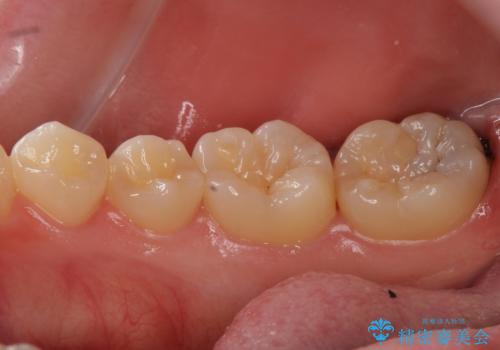

比較的大きな虫歯でしたがゴールドでの修復にすることで歯の削る量を抑え、精度の高い治療を行うことができました。